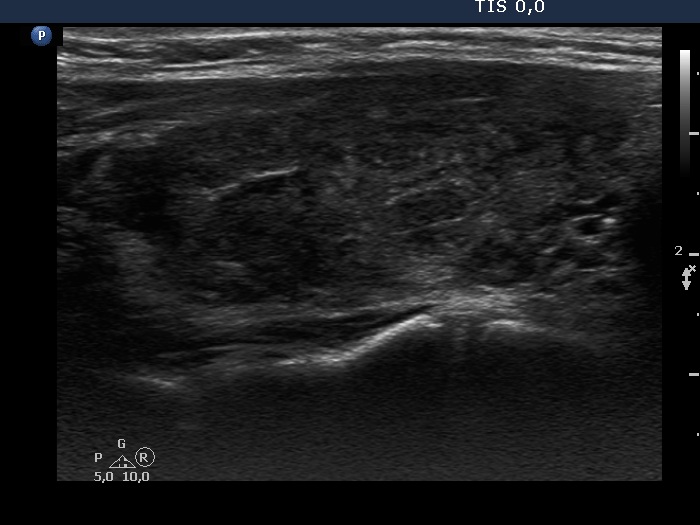

Consecutive patients with the final diagnosis of Hashimoto's thyroiditis - case 28 (481) (ultrasonographic picture 3)

Right lobe, another longitudinal view. Note fibrotic changes.